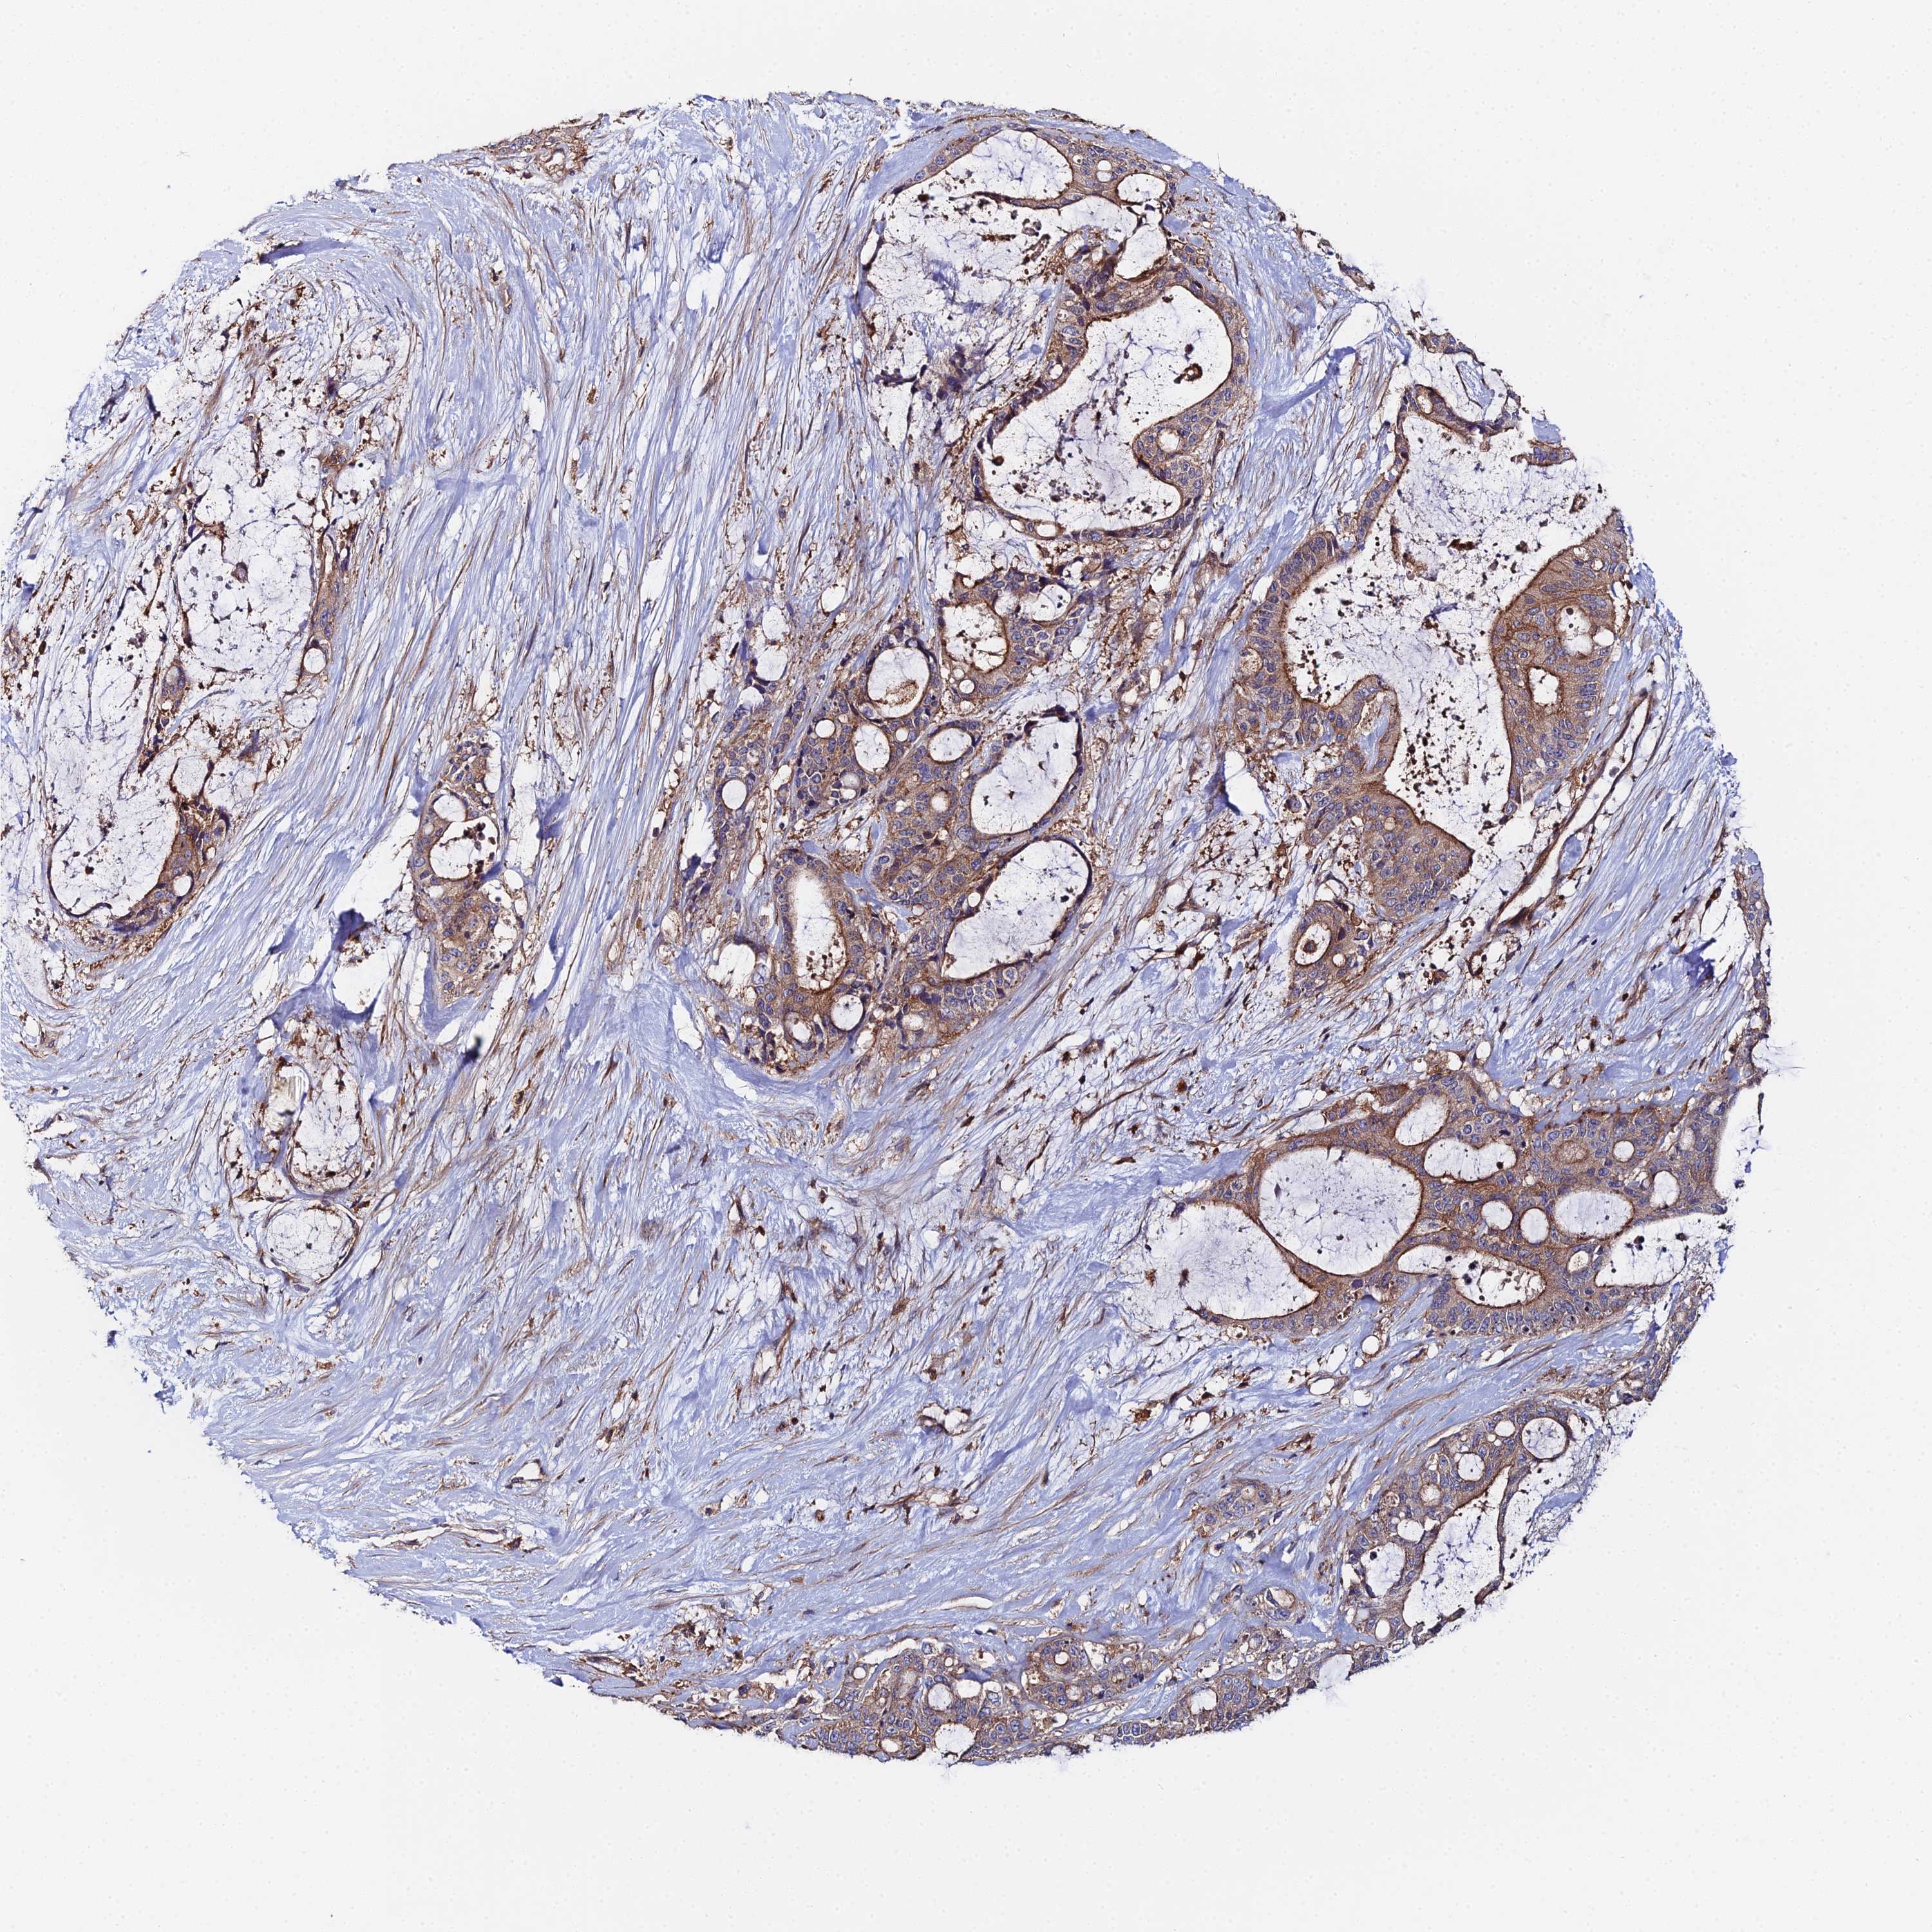

LIVER CANCER - Protein expressioni

A mouse-over function shows sample information and annotation data. Click on an image to view it in a full screen mode. Samples can be filtered based on level of antibody staining by selecting one or several of the following categories: high, medium, low and not detected. The assay and annotation is described here.

Note that samples used for immunohistochemistry by the Human Protein Atlas do not correspond to samples in the TCGA dataset.

Antibody stainingi

Antibody staining in the annotated cell types in the current human tissue is reported as not detected, low, medium, or high, based on conventional immunohistochemistry profiling in selected tissues. This score is based on the combination of the staining intensity and fraction of stained cells.

Each image is clickable and will lead to virtual microscopy that enables deeper exploration of all samples and also displays staining intensity scores, fraction scores and subcellular localization as well as patient and tissue information for each sample.

Antibody HPA043651

Antibody CAB032623

Staining

High

Medium

Low

Not detected

Intensity

Strong

Moderate

Weak

Negative

Quantity

>75%

75%-25%

<25%

None

Location

Nuclear

Cytoplasmic/membranous

Cytoplasmic/membranous,nuclear

Cholangiocarcinoma

Carcinoma, Hepatocellular, NOS